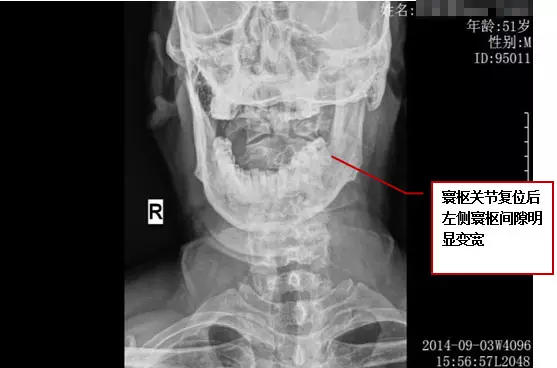

段先生,男,51岁,云南人,于2014年9月2日慕名而来,由我院赖志刚院长接诊。

客观检查结果: 复位前 拍片时间: 2014年9月2日 18:43

客观检查结果:复位后 拍片时间: 2014年9月3日 15:56